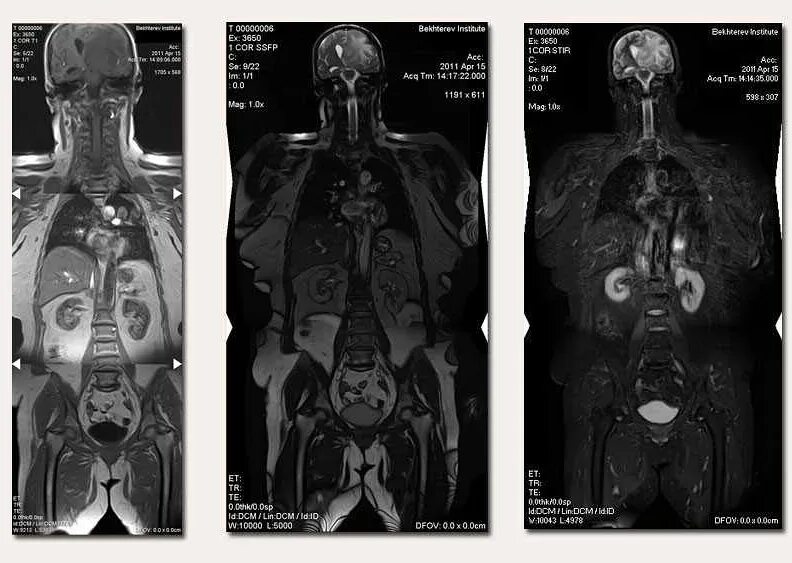

Мрт полностью